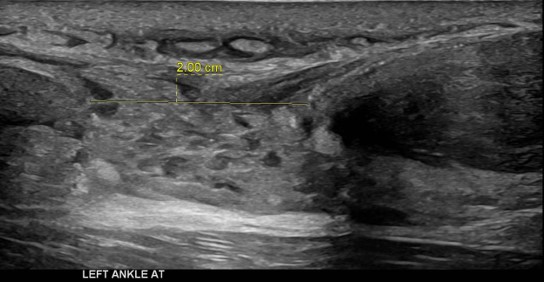

Athletes in running sports have a high incidence of Achilles tendon overuse injuries. About 75% of total tendon ruptures and the majority of partial tendon ruptures are related to sports activities usually involving abrupt repetitive jumping and sprinting movements.

The push off movement uses a strong contraction of the calf muscles which can stress the Achilles tendon too much. Ultrasound findings demonstrated here show a complete Achilles tendon rupture, the measurement is of the gap width between the tendon free edges. Oedema is noted filling the gap.